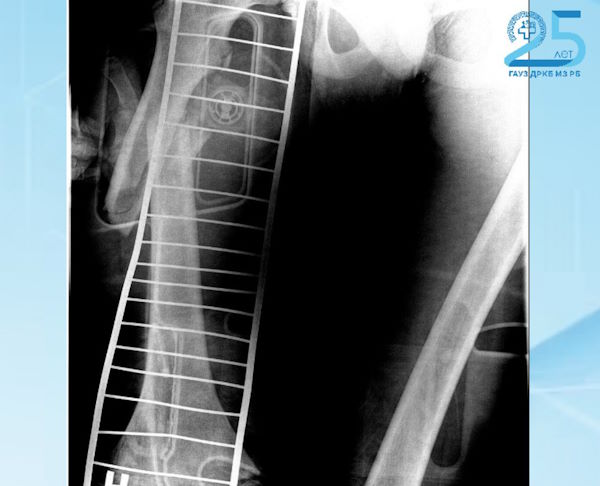

В одном из районов республики двое 15-летних подростков при управлении мотоциклом попали в ДТП и также столкнулись с автомобилем. Их обоих госпитализировали в отделение анестезиологии и реанимации, а после переведели в отделение. У подростков диагностированы множественные травмы, среди них перелом бедренной кости со смещением — у одного, перелом большеберцовой кости со смещением — у другого.